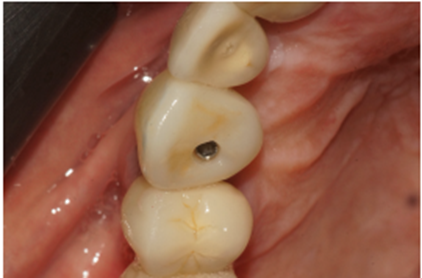

O caso clínico a seguir irá descrever o sucesso dessa nova realidade. Paciente J.C., de 65 anos de idade, do sexo masculino, compareceu em minha clínica com o elemento 13 fraturado (Figura 1). Após análise criteriosa da tomografia, foi planejada a exodontia e a instalação imediata do implante seguindo as novas tendências no posicionamento tridimensional, isto é, a melhor posição no rebordo na relação dento alveolar (Figura 2). Foi realizada a terapia medicamentosa com a administração de Amoxicilina 500 mg, de oito em oito horas durante sete dias, iniciando um dia antes do procedimento, e o uso de anti-inflamatório após a cirurgia, durante três dias. A exodontia foi realizada de forma atraumática, como sugerido na literarura (Figuras 3 e 4) e foi realizada a fresagem para a instalação de um implante Due Cone Implacil De Bortoli (conexão morse) de 3.5 x 13 mm, que foi estabilizado a 46 Ncm (Figuras 5, 6 e 7). Após a instalação, o gap foi preenchido com biomaterial, um cicatrizador de 5.5 X 3.5 mm (diâmetro/altura) foi instalado e o tecido foi suturado ao seu redor, protegendo assim o biomaterial (Figura 8).

Figura 1 – Análise inicial